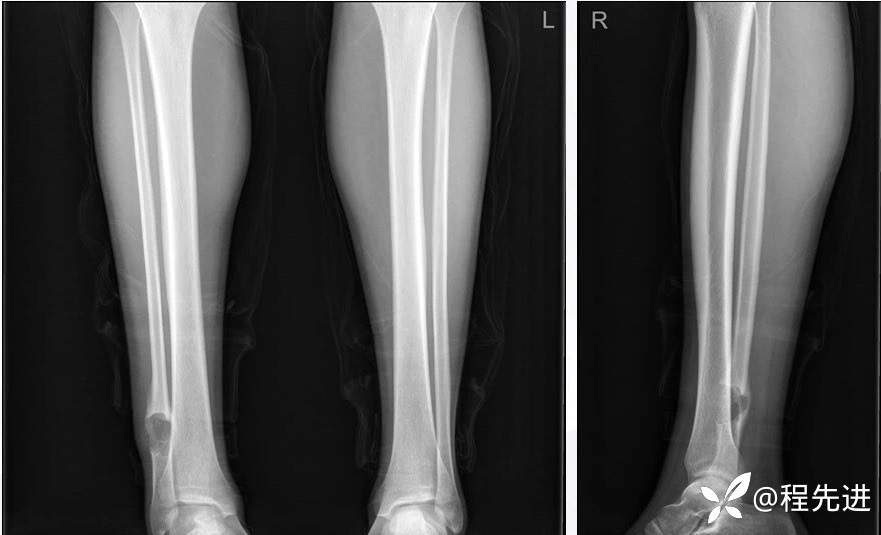

DR